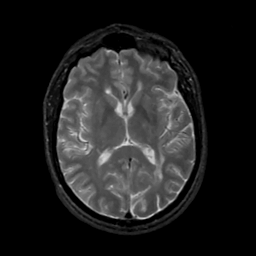

MR Study #2, February 17, 1991 -- Slice #27

[Home][Help][Clinical][Tour 1][Tour 2] Slice 27